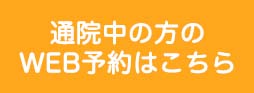

人間の頭と顔は、上から下へと成長が進みます。まず成長のピークは、頭蓋→上顎→下顎の順番で起こります。

顎は先に上顎が大きくなり少し前に出て、その後身長が伸びる同じ時期に下顎が大きくなり前に出ることで、上下顎のバランスをとります。受け口のままでは、上顎の成長のピークが来ても下顎が上顎の成長を邪魔してしまい、上顎は大きくなれません。その後、下顎の成長のピークが来ると、下顎は前に伸び放題になってしまい、ますます下顎前突(受け口)がひどくなってしまいます。

また受け口が治ったからといって、短期間で下顎前突の治療をやめてしまうと、最後に下顎の成長のピークが来るため、受け口が戻ってしまうのです。

当院の小児矯正では、お子様の成長を利用してその子の理想の顎骨の大きさ、さらに良好な上下の顎のバランスへと成長を促すことで、下顎前突を治します。大切なことはお子様の成長期のスパートが起きる前に早くから小児矯正を開始して、下顎の成長の終了(身長が止まる)まで経過観察を継続することです。

成長を利用した小児矯正では上下の顎の成長のピークを知ることが、とても重要となります。